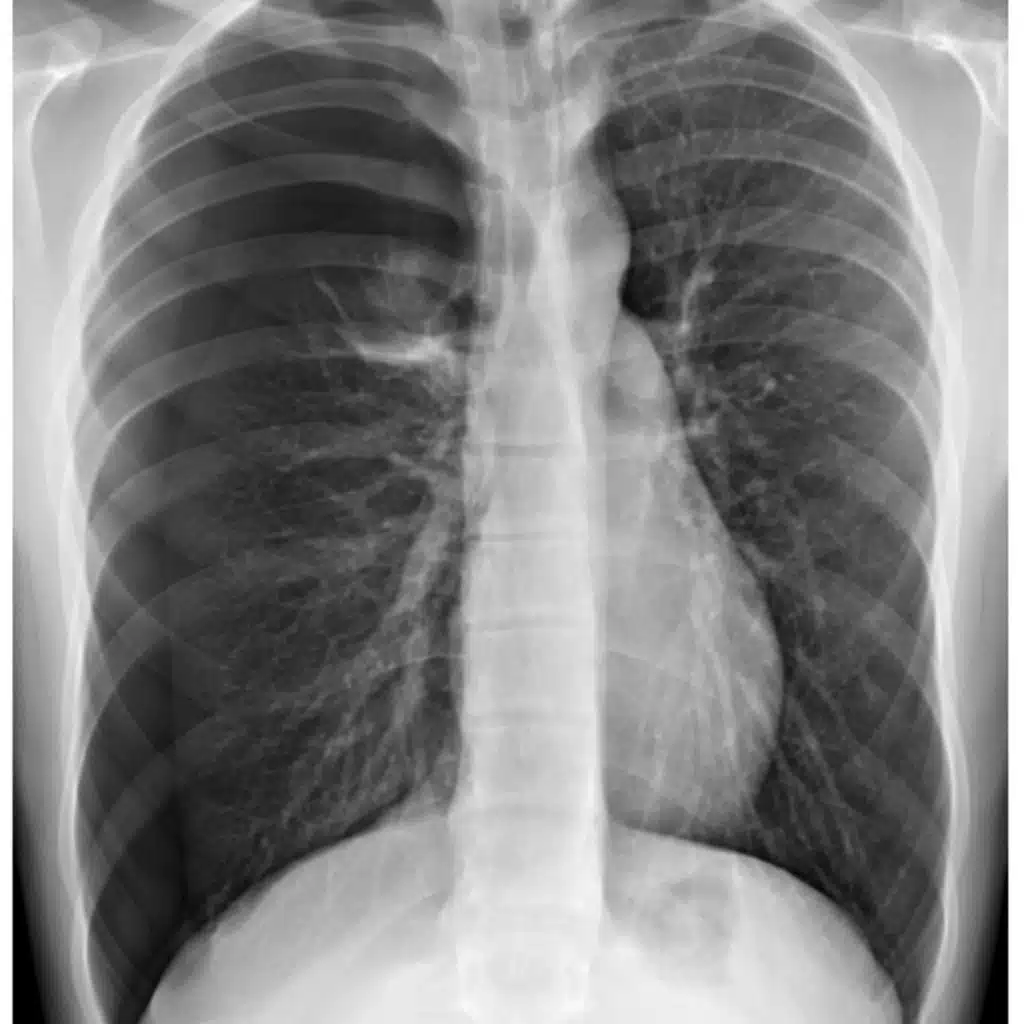

Episode 183.0 Pneumothorax

A quick overview of pneumothorax for the EM physician: the what, why, diagnosis, and treatment.